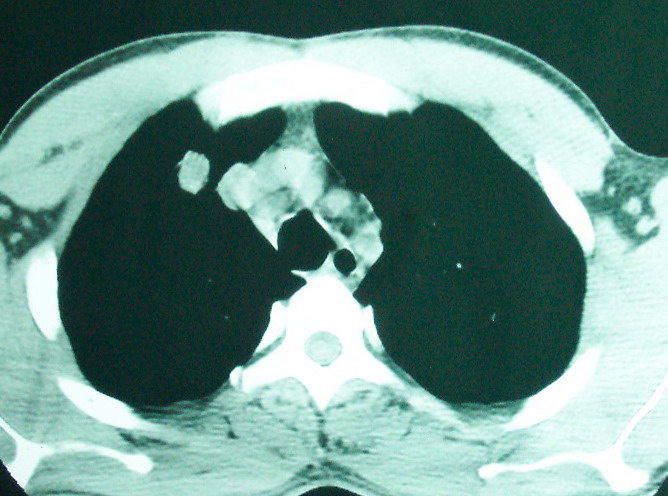

m      37y      发热   咳脓痰月余      ct肺脓肿但住院抗炎治疗后双肺内结节不知该如何解释

治疗后见左肺下野病灶较前缩小但双肺内结节影似无变化请较各位老师该如何下结论    治疗前wbc14.5 治疗后wbc 11.0

如果你仔细的同层面对比,你会发现所有的病灶均有比较明显的吸收、缩小。病变的形态,特别是脓肿的形态、壁的厚薄、内壁均有很大的变化,均在往好的方面发展。与临床症状、血像均符合,治疗效果比较显著,就是肺脓肿并双肺的化脓性炎症灶。